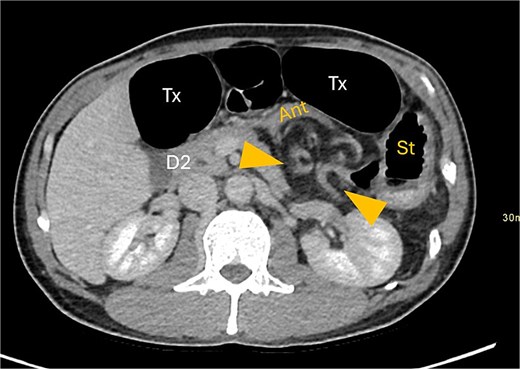

A contrast-enhanced computed tomography (CT) scan of the abdomen and pelvis demonstrated a large bowel obstruction with a transition point at the distal transverse colon with swirling of the mesentery. Downstream large bowel was collapsed. Upstream dilatation included the terminal ileum suggested an incompetent ileo-caecal valve. The gastric antrum was also involved in the internal hernia, resulting in gastric outlet obstruction. See Figs 1–5.

Axial CT image displaying transverse colon in paraduodenal hernia (PDH) with resulting distension of transverse colon (Tx) and stomach (st).

Gastric outflow obstruction of stomach (st) from compression of antrum (ant) by herniated transverse colon. Hernia between arrows.